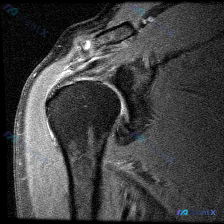

刚整理完一份肩部MRI读片病例,病例本身不复杂,但很容易只看到表面的积液忽略根本问题,分享给大家,整理一下完整的分析思路。 病例影像基础信息 本次读片基于肩部MRI-T2序列冠状位影像,核心初始发现是软组织积液,我们来逐层拆解: 影像学客观发现 1. 冈上肌肌腱:在肱骨大结节附着点(足印区)区域,肌...

最近看到这份肩部MRI病例,问题问的是影像里的软组织积液怎么解释,整理了完整的读片和分析思路分享给大家。 一、影像基本信息 这是一张肩关节冠状位T2序列MRI,扫描范围覆盖肩峰、肩锁关节、冈上肌肌腱、肱骨头、肩关节间隙和三角肌,我们先明确正常信号基准:T2序列正常肌腱是低信号(黑色),关节液、水肿是...